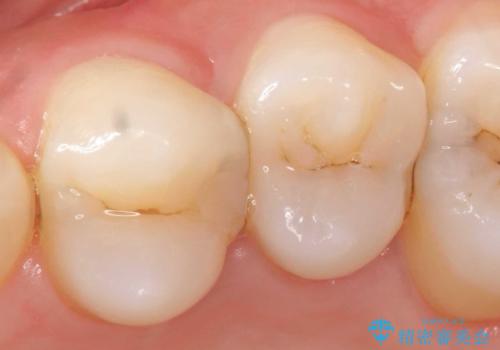

神経近くにまで及んだ大きなむし歯のセラミッククラウン